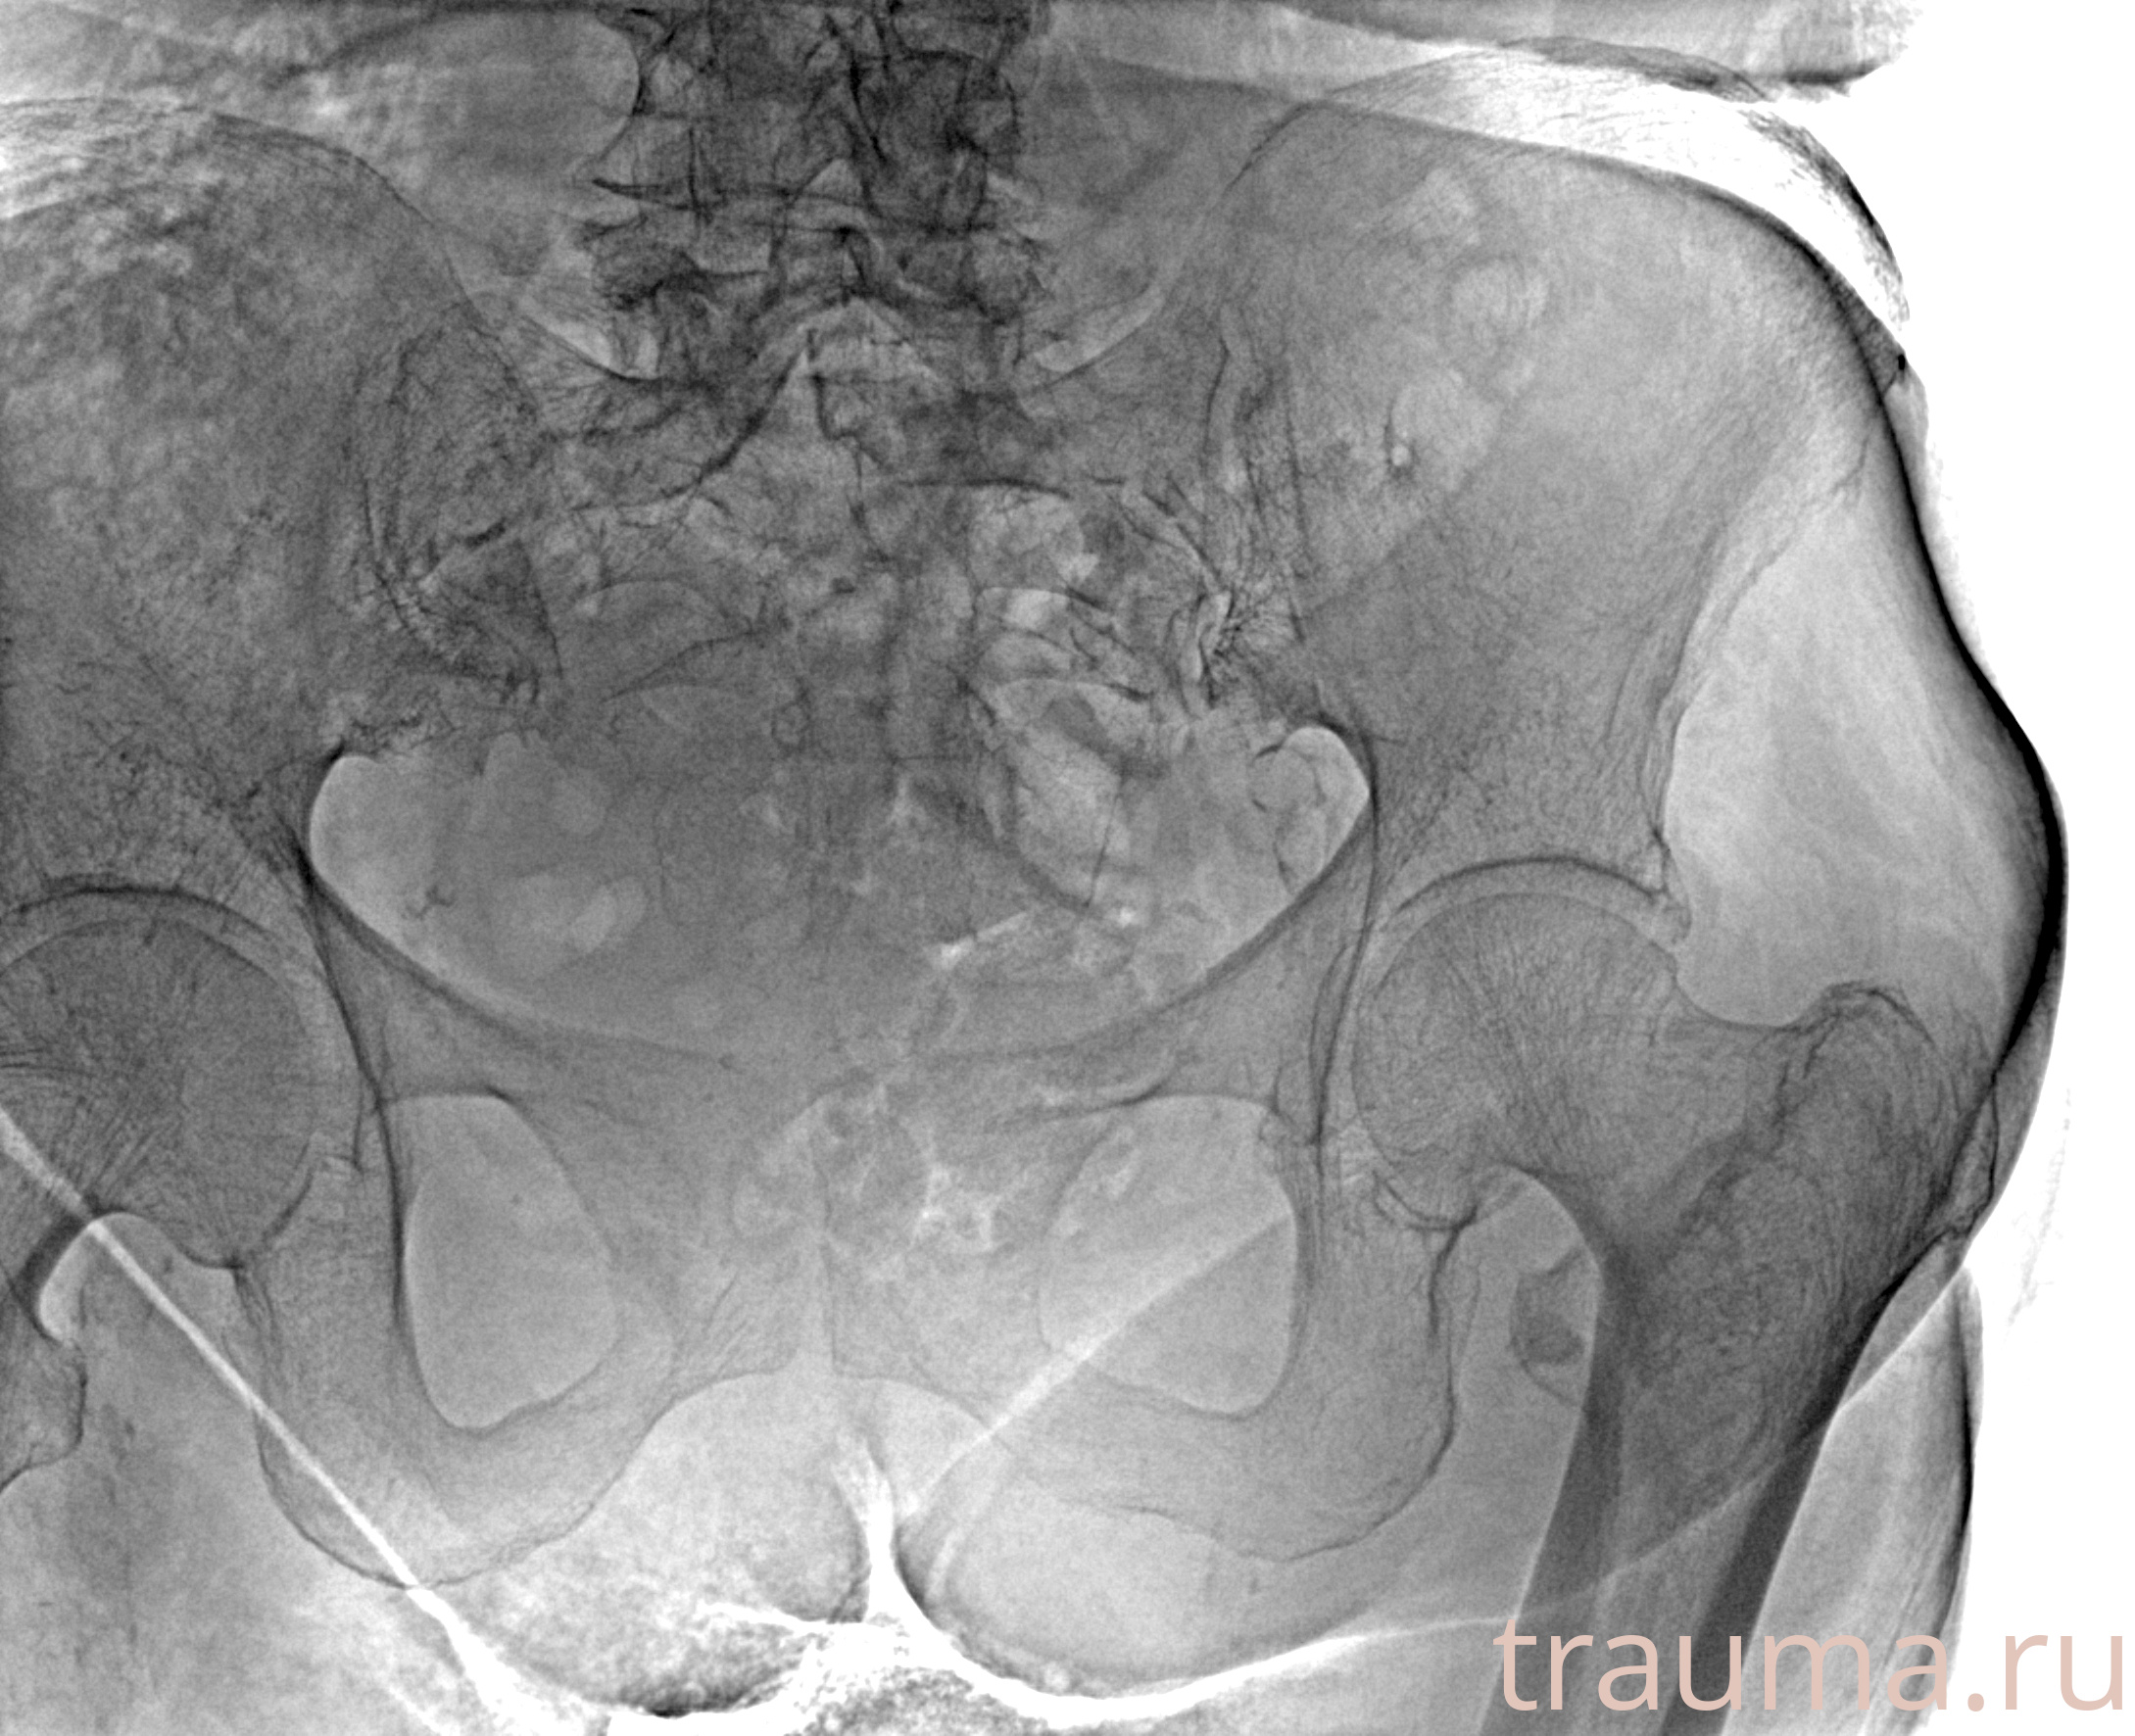

Рентген на дому: по вашему адресу приезжает врач-рентгенолог, травматолог-ортопед с мобильным рентгеновским аппаратом, проводит диагностику травмы или заболевания, делает необходимые рентгенограммы, дает рекомендации по дальнейшему лечению. Получить качественные снимки в домашних условиях возможно благодаря уникальной методике, разработанной МосРентген Центром для института  Склифосовского